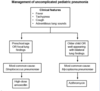

Pt with hemoptysis comes in with [Solitary Pulmonary Coin Nodule] on CXR

What are the 3 [preDiagnostic Mgmt] steps for SPN?

A: LOCATE PREVIOUS CXR ≥ 1y old!

_________________

b: If SPN unchanged = NO CA

C: If [(SPN ∆) OR (NO PRIOR CXR)] ➜ [Diagnostic Mgmt] (image)

Coin lesions = 80% chance malignancy

List 5 characteristics of [solitary pulmonary coin nodules] that help to determine their Malignancy & workup

Smoking hx | Location | Age | Border || size

-Smoking Hx

-Location: Endobronchial proximal extension/Local invasion/Satellite Nodules

-Age

-Border: : Spiculated / Retracted from surrounding tissue / irregular

-size: {≥8mm}

After the [SPN 3-step prediagnostic mgmt]

How do you workup [Solitary Pulmonary Coin Nodule]?